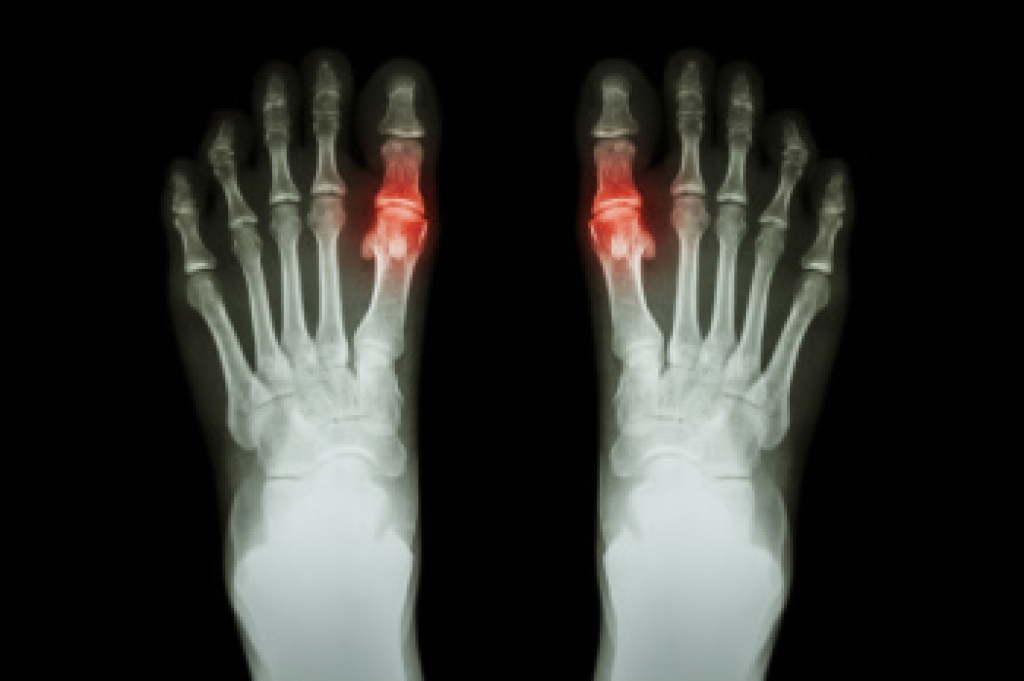

Morton's neuroma is a painful condition affecting the ball of the foot, typically between the third and fourth toes. It is not a true neuroma but can be debilitating, causing numbness, burning, or tingling. The condition often develops due to chronic trauma from repetitive pressure or activity, entrapment of the nerve between the metatarsal bones, inflammation of the intermetatarsal bursa that cushions the area, or damage from reduced blood flow. Chronic trauma refers to repeated stress that irritates the nerve, entrapment occurs when the nerve is compressed, bursitis causes swelling and irritation, and poor blood flow limits oxygen supply to the tissues. A podiatrist can diagnose the condition, recommend orthotics, footwear modifications, injections, or surgical options, if necessary. If you have pain in this part of your foot, it is suggested that you schedule an appointment with a podiatrist for an expert evaluation and effective relief solutions for what may be going on.

Morton's neuroma is a painful foot condition that commonly affects the areas between the second and third or third and fourth toe, although other areas of the foot are also susceptible. Morton’s neuroma is caused by an inflamed nerve in the foot that is being squeezed and aggravated by surrounding bones.